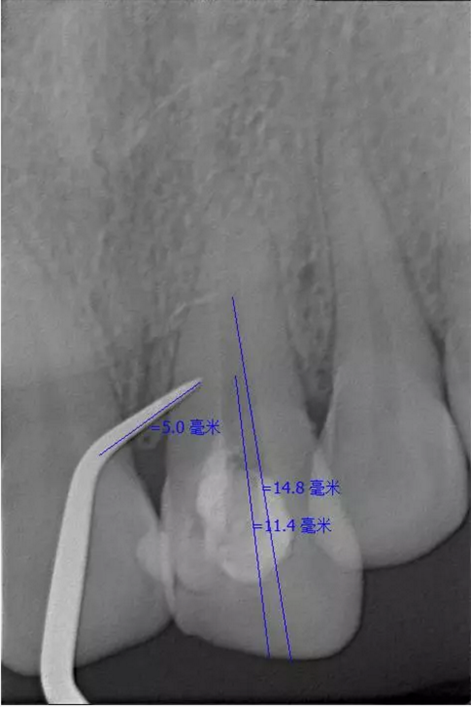

翻瓣去除側(cè)穿超出的牙膠尖

側(cè)穿超出的牙膠尖

患者女,年齡35左右,牙位21,根管治療曾經(jīng)歷過外院四到五次等不同地方的處理,還是不能咬硬物,會(huì)有酸、軟、痛的情況出現(xiàn),偶有自發(fā)疼痛,2016年9月初,轉(zhuǎn)診至我處治療21。術(shù)前拍片發(fā)現(xiàn)根中部存在側(cè)穿,橡皮障下常規(guī)再治療,隨后減輕了軟和痛的情況。因?yàn)閭?cè)穿,牙周膜受到牙膠尖等異物的持續(xù)刺激,酸軟的情況還是持續(xù)存在,所以決定行根尖外科手術(shù),采用MTA修補(bǔ)穿孔點(diǎn)。術(shù)后觀察半年左右,所有癥狀消除后,隨后熱牙膠充填。